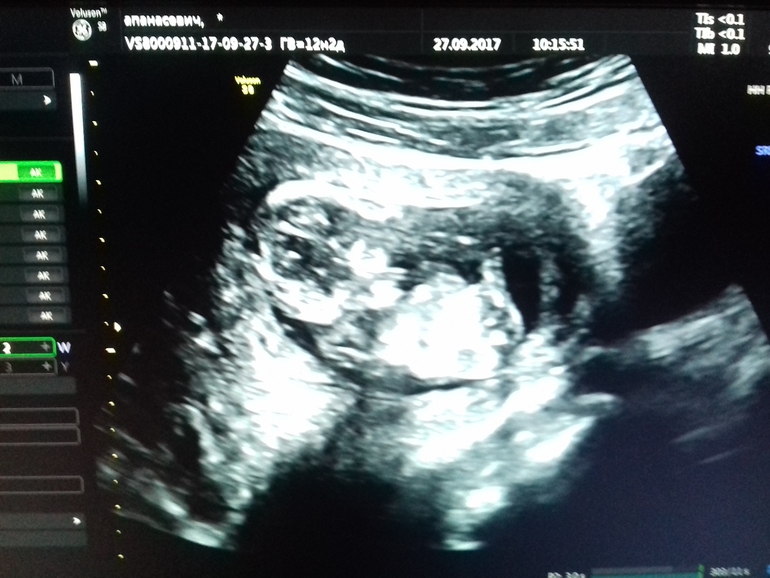

Кто же у нас?😏

Это первый скрининг, врач сказала 50 на 50 (узи делала бесплатно в жк, и поэтому думаю что врач сильно не напрягалась)))

Срок на время узи был 12.6 (по мес. 12.2)

На таком сроке определяют по половому бугорку) У девочек он немного наклонён вниз или вдоль позвоночника, а у мальчиков приподнят

вверх) Вот моё УЗИ на 12 неделе, я выделила этот самый половой бугорок, аппарат был хороший и узист очень опытный, сказал что скорее всего девочка, не давно подтвердил на 16 неделе))

Половой бугорок не различим, по углу его наклона определяют пол на этом сроке. А у вас при таком ракурсе не видно

Алёна, да дело то даже не в качестве, просто фото на котором видно пол, должно быть сделано со стороны попы, у меня так было. А в таком ракурсе никто и никогда не увидит)

А у вас, я так понимаю стандартное фото, когда бочком всего малыша видно

Первый скрининг в 10-12 недель совсем не показательный в плане пола. Тут дело не во враче. На этом сроке половые органы девочки и мальчика внешне очень похожи. Бугорок может быть либо будущим пенисом, либо клитором. К 17 неделям уже будет возможно определить пол без проблем.